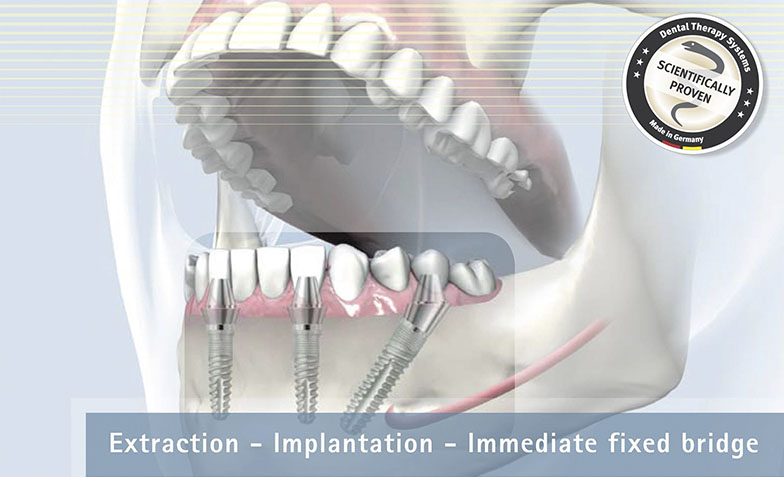

Sistemul Fast&Fixed este o alternativă imediată. Această procedură îți va permite să-ți recapeți zâmbetul și încrederea în sine într-un timp scurt. Deși rezultatul este imediat, durata de viață a acestui implant este pentru o perioadă îndelungată.

Este un sistem inovativ care permite o fixare rapidă și de lungă durată a dinților lipsă. În acest caz se folosește osul nativ al pacientului. În acest fel sunt eliminate alte intervenții adăugătoare, cum ar fi creșterea masei osoase. Acest sistem presupune doar câțiva pași: consultarea, elaborarea unui set de analize, amprentarea dentară, inserarea implanturilor provizorii, refacerea arcadelor dentare, iar la final fixarea danturii definitive. De la consultare până la obținerea unui zâmbet impecabil te despart doar 24 de ore.